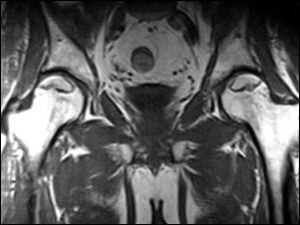

Pelvik tabanın leğen kemiğinin alt kısmında bulunan kas-bağ dokulardan oluşan bir yapı olduğunu ifade ederek sözlerine başlayan Doç. Dr. Turgut, “Bu da leğen kemiğindeki organlarımızı koruyor ve işlevlerine yardımcı oluyor. Pelvik tabanda mesane, rahim, genital organlar ve bağırsağın son kısmı dediğimiz rektum gibi organlar bulunuyor” diyor.